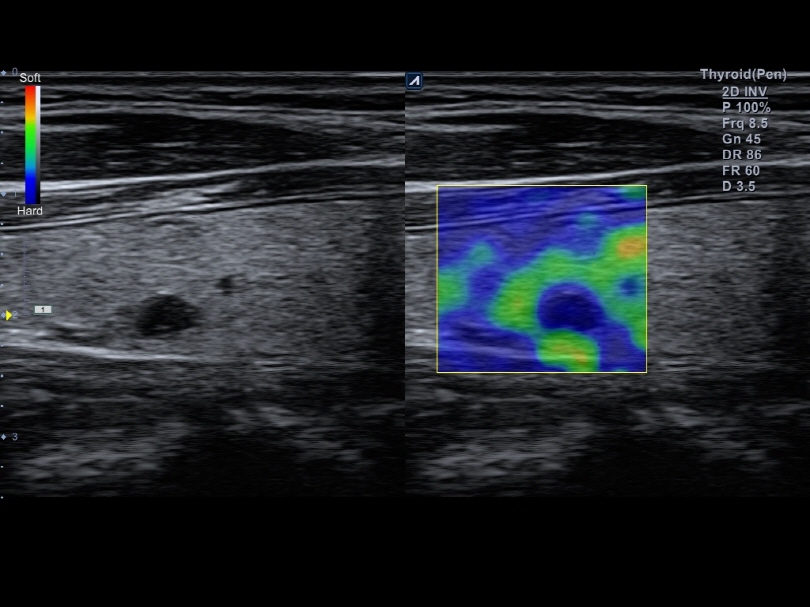

L8-17H

High density linear transducer(8-17MHz)

Application:

Breast, EM, MSK, Vascular, Small Parts

L3-12H

High density linear transducer (3-12MHz)

Application:

Breast, EM, MSK, Vascular, Small Parts

L3-12HWD

High density wide footprint linear transducer (3-12MHz)

Application:

Breast, EM, MSK, Vascular, Small Parts, Appendix

L3-12T

Linear transducer (3-12MHz)

Application:

Breast, EM, MSK, Vascular, Small Parts, Appendix